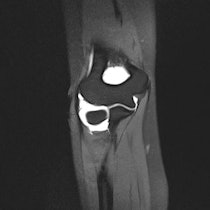

The London 2012 medical team is preparing to treat sports injuries like this partial thickness injury of the distal ulnar collateral ligament, diagnosed by an elbow MR arthrogram. Image courtesy of Dr. Phil O'Connor.